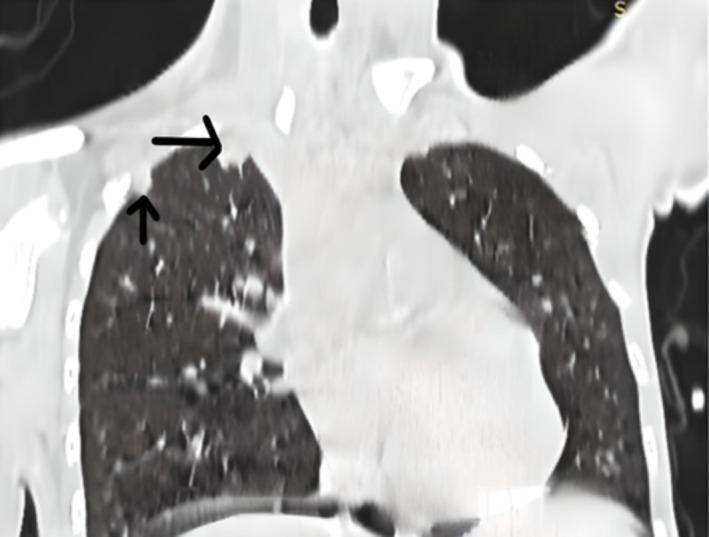

Poorly Differentiated Aggressive Sacral Chordoma With Upfront Lung Metastases in a Child-A Case Report.

Poorly differentiated chordoma is a very unique type of chordoma with a particularly aggressive clinical course and high metastatic potential. It almost exclusively affects children and young adolescents. Unlike conventional chordomas, poorly differentiated chordomas cannot be well controlled with surgery and radiation therapy. Systemic agents are required for the treatment of this aggressive malignancy.